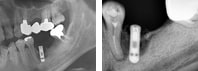

08.02.15 인공뼈

이식술 후, 사진

: 잇몸뼈가 재생된 후,

임플란트 재식립을

하였고, 보철 제작

시행 전, 임플란트와

잇몸뼈 사이의 결합도를

확인하였다.